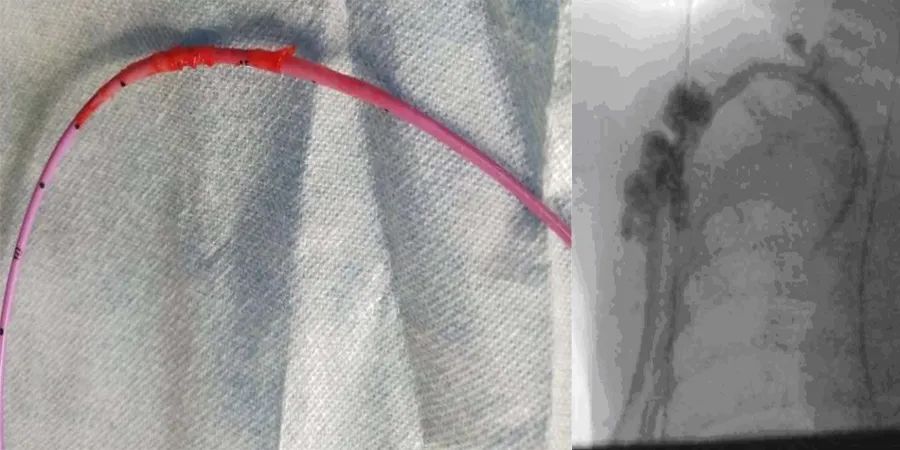

将导管更换为Medcomp®10 Fr×15 cm分离式导管®,通过一个稍微位于前一切口内侧的新切口插入右侧颈内静脉。选择大口径、短导管,以达到更高的流速和避免导管尖端的移动。影像增强确认位置,两腔在手术室冲洗和抽吸良好。放置导管后,立即尝试血液透析,但尽管冲洗良好,动脉腔仍无法抽吸,患儿明显疼痛。影像学检查显示对比剂似乎从多个部位逃逸到周围组织中(图1c)。立即取出导管,用一个位于右心房的12-Fr剥离式鞘管通过上一个切口替换成新导管。在检查或冲洗拆除的管线时,未发现断裂迹象。影像增强确认了新透析通路的位置,在肝素封管前,两个管腔在手术室抽吸和冲洗良好。

通过导管缓慢注射造影剂可以区分导管尖端血栓(造影剂喷射出导管时不规则)和导管尖端粘连血管壁(远离导管尖端的造影剂不对称或倾斜流动)。在这个病例中没有观察到这些迹象,故怀疑纤维蛋白鞘的存在。体内导管末端局部纤维蛋白鞘形成,DSA下可见沿体内导管外壁走形的线样、柱状或不规则状高密度影,包裹体内导管末端及侧孔,造影剂向上反流进入腔静脉;体内导管广泛性纤维蛋白鞘形成,DSA下可见沿体内导管外壁走形的不规则状高密度影,包裹整个或大部分体内导管,造影剂向上反流可进入植入侧皮下软组织内。纤维蛋白鞘的存在常被误认为导管破裂所致的外渗。在这个病例中,在取出导管后的检查中,没有发现管线断裂。